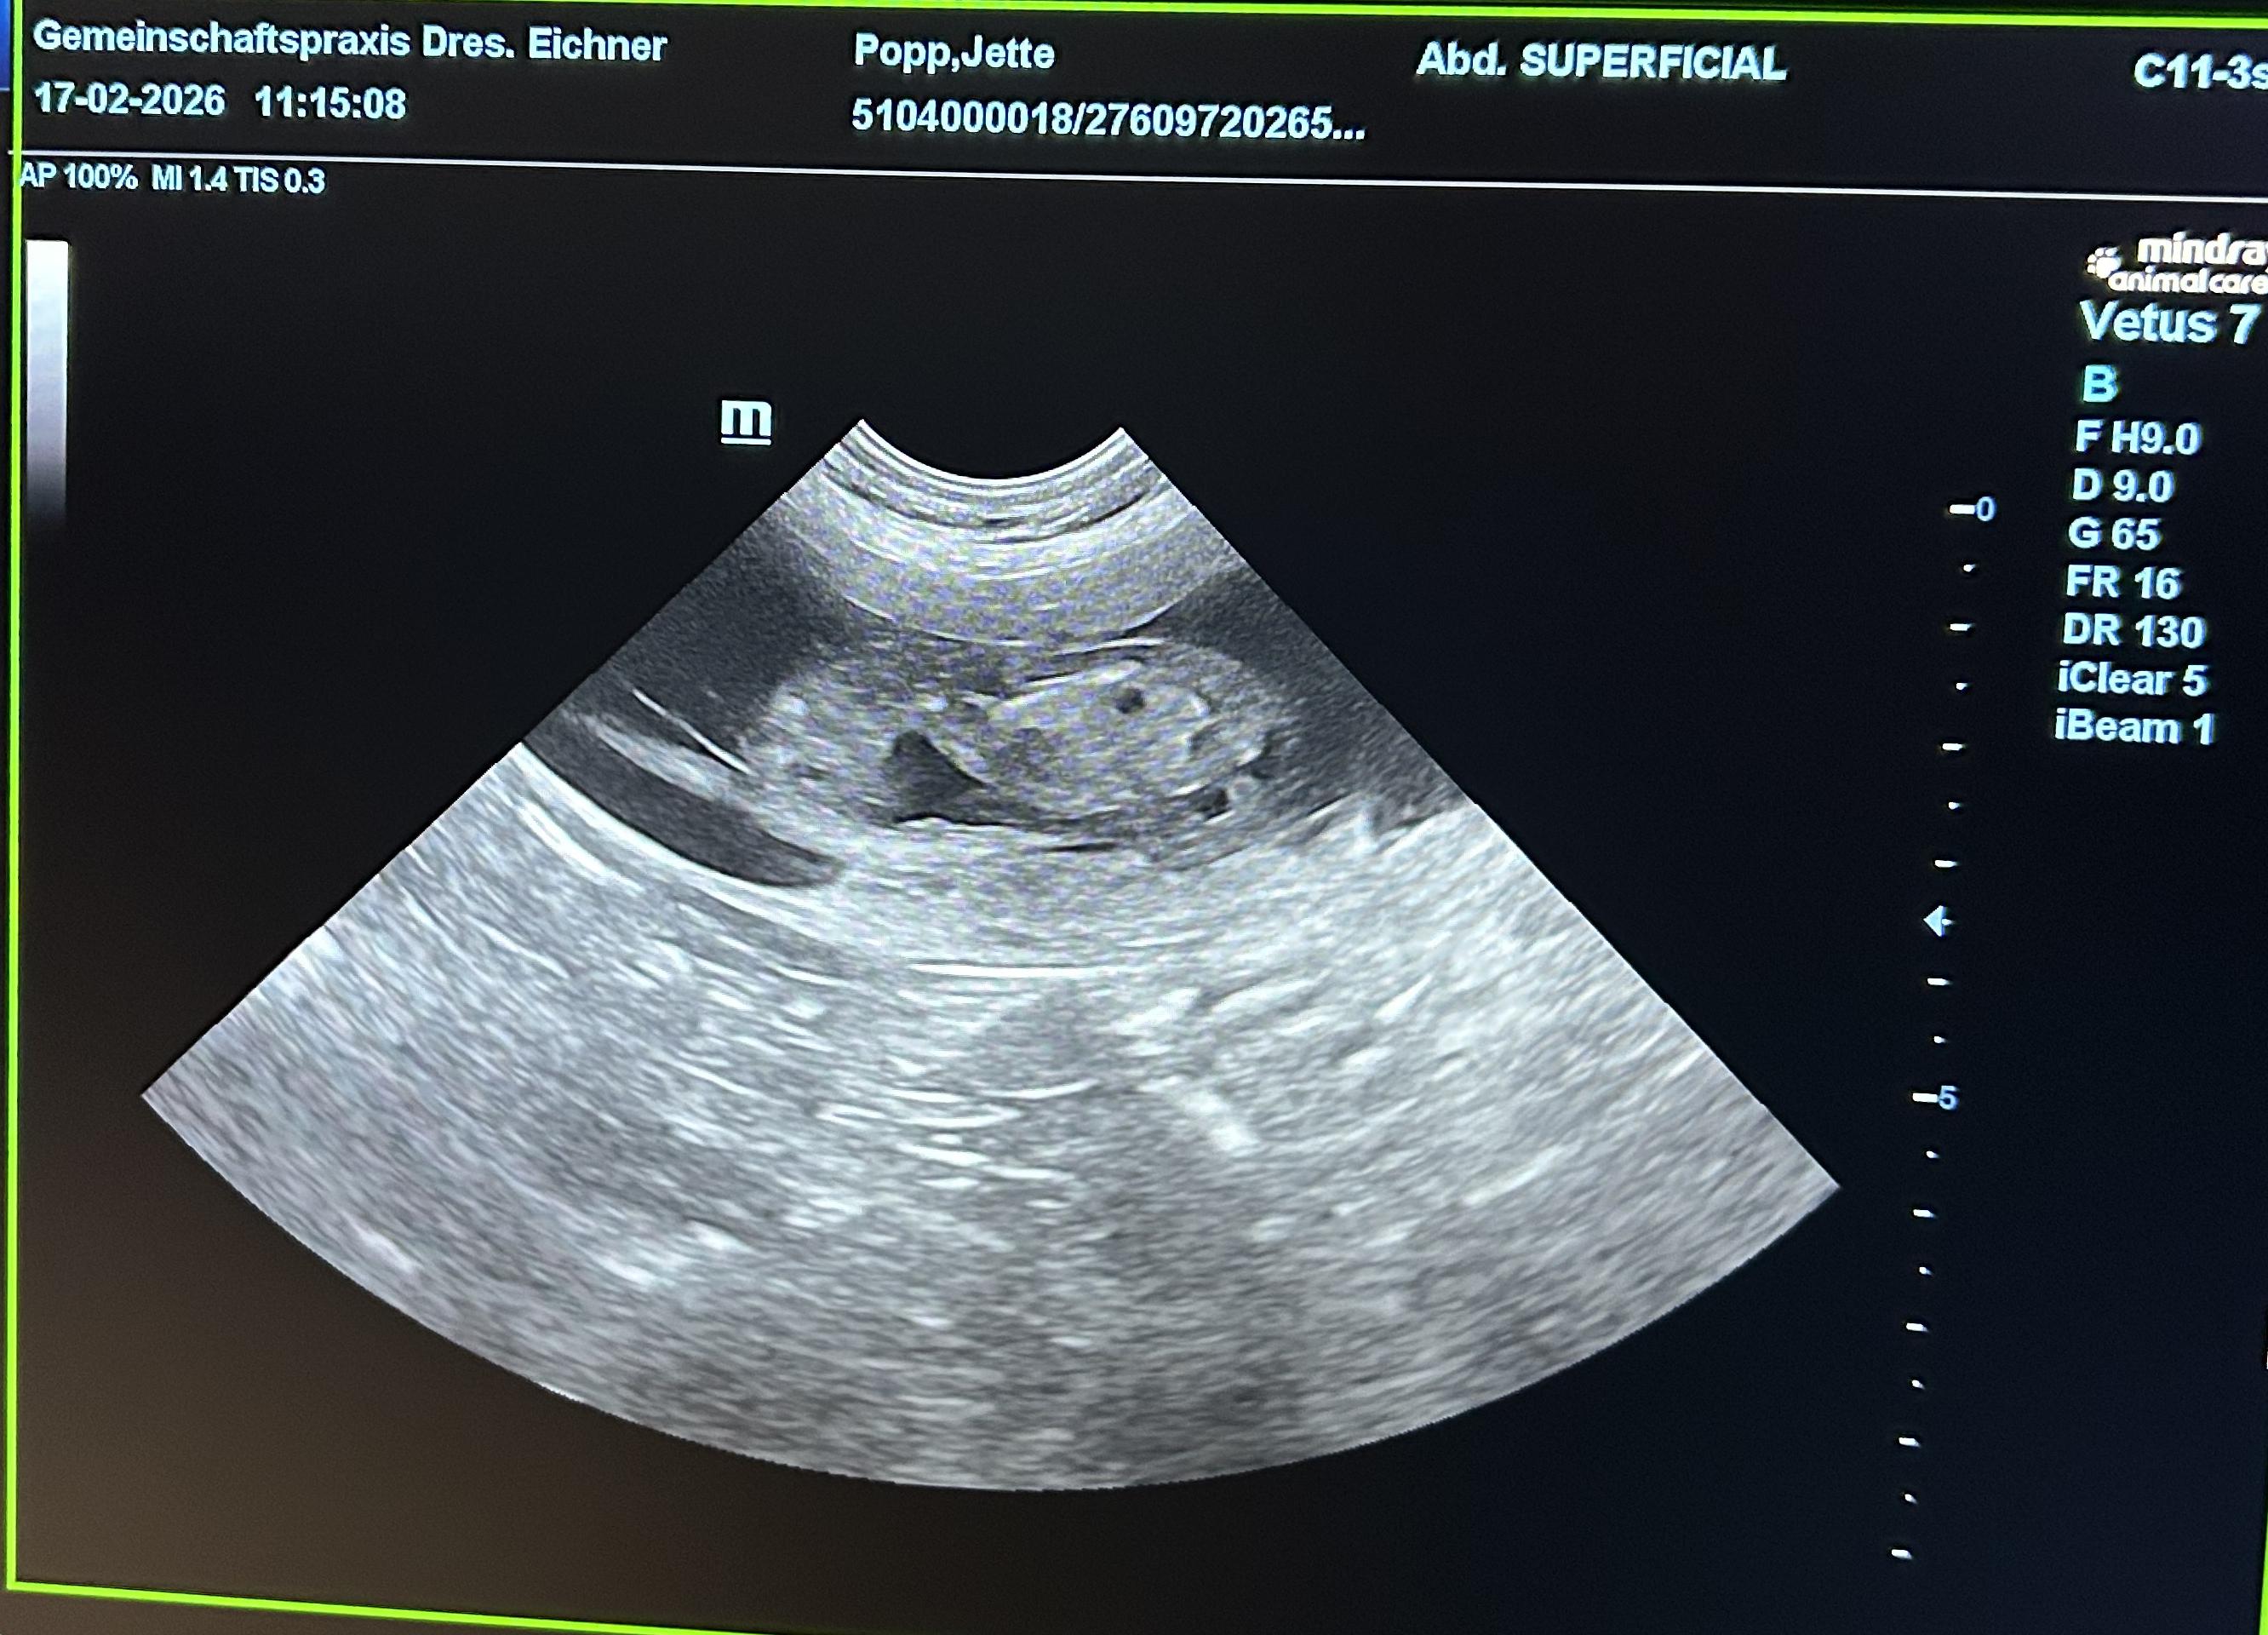

Jettes Welpen 2026

Dt.J. Ch. VHD & Club Scottsdale Xircus as Nonchalance "Jette" |